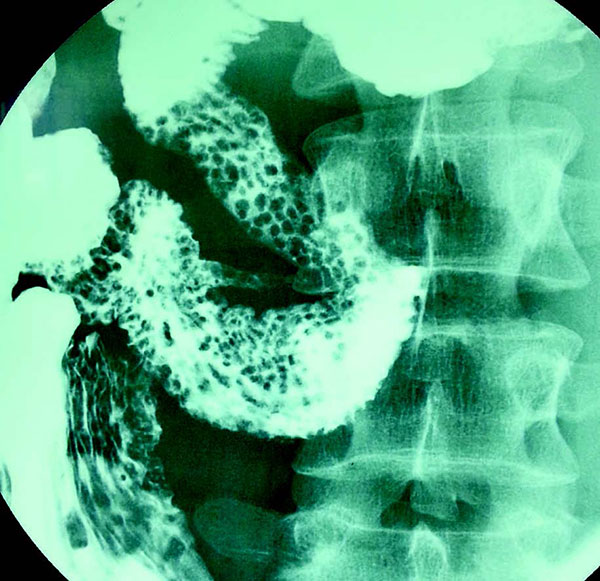

患者男,32岁。12岁时被诊断为复发性鼻窦炎、支气管炎和扁桃体炎。患者自述腹泻2周余。影像学示结节性淋巴组织增生:

下列哪种疾病可出现这些特殊的影像学图片?

答案:B